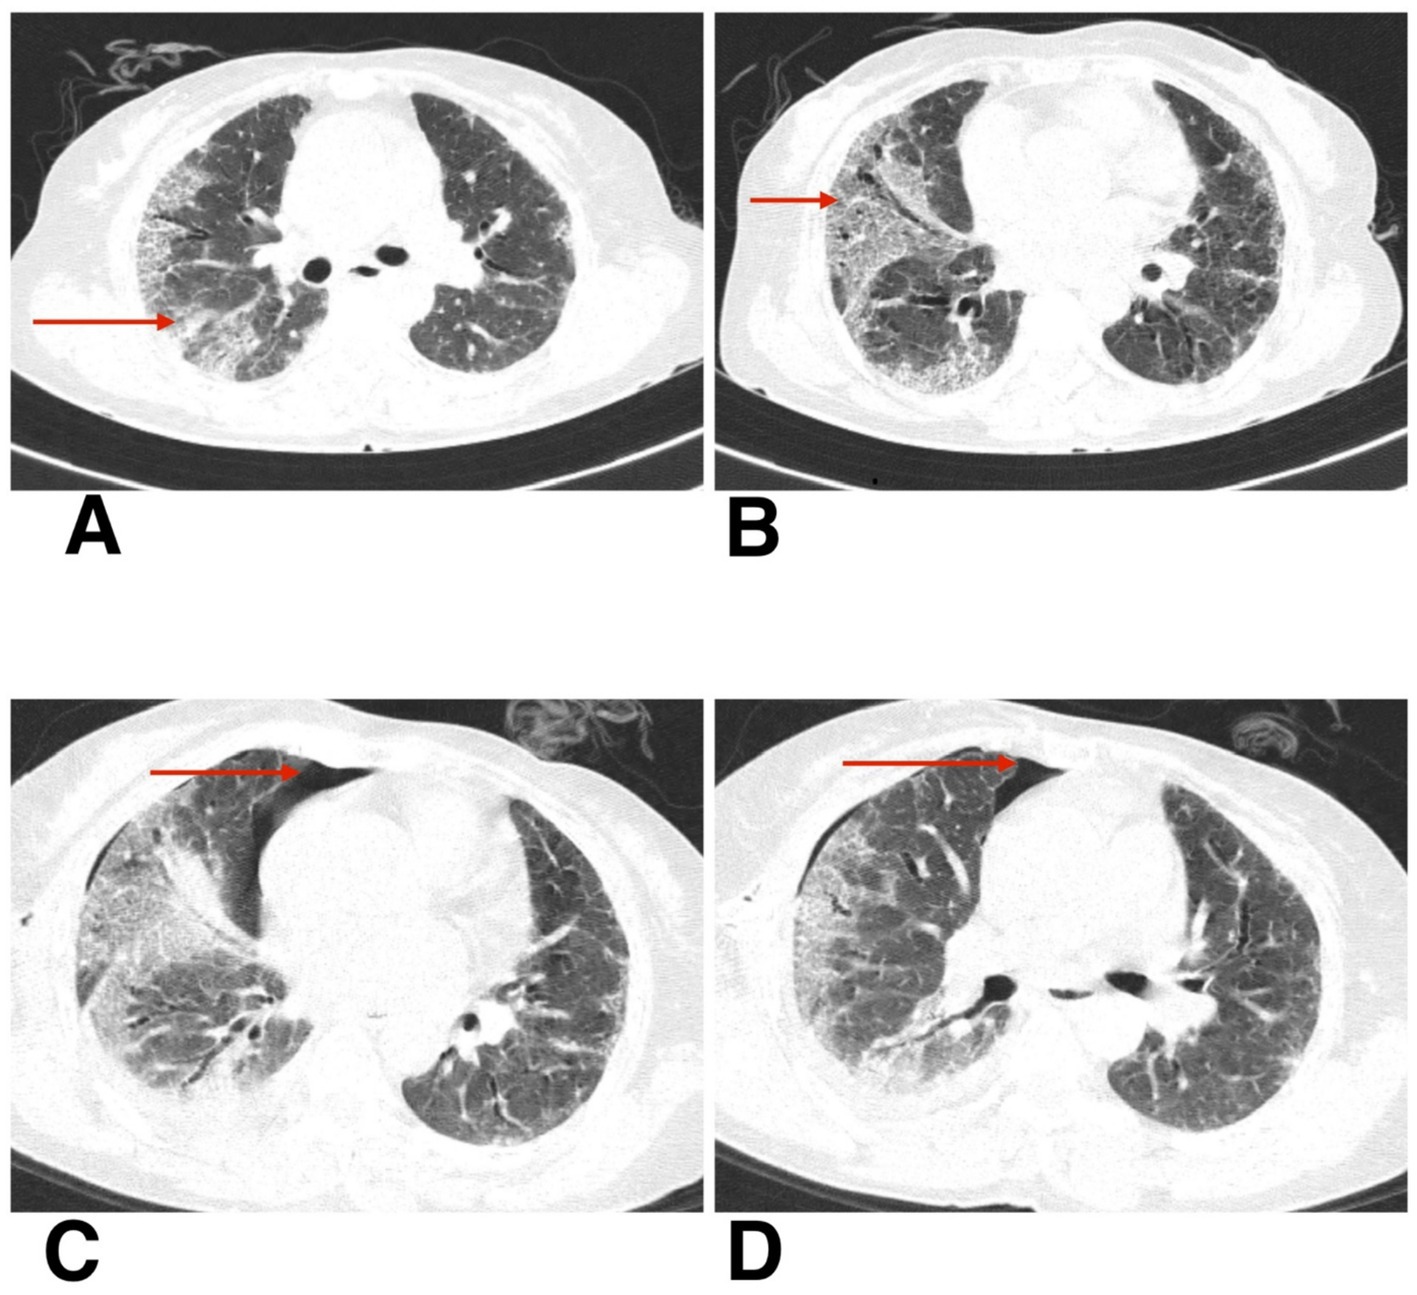

Radiological evaluation with chest X-ray showed reticular opacity in the right lower zone (Figure 4A), and HRCT thorax demonstrates extensive subpleural and basal reticular opacities, peripheral traction bronchiectasis, and a crazy paving pattern, consistent with a probable usual interstitial pneumonia (UIP) pattern (Figures 5A,B).

Figure 5. (A,B) HRCT thorax of axial section shows peripheral traction bronchiectasis, and a crazy paving pattern, consistent with a probable usual interstitial pneumonia (UIP) pattern. (C,D) HRCT thorax of axial section shows resolving pneumothorax after intercostal drainage and residual pneumothorax (red arrow).

The second patient was hospitalized for 8 days during her initial presentation and treatment. Following discharge, she returned for a scheduled outpatient evaluation 2 weeks later. At this visit, she reported increased shortness of breath and chest discomfort. On presentation, her SpO₂ was 91% on room air. Supplemental oxygen was administered via nasal prongs at a flow rate of 4 L/min, titrated to maintain oxygen saturation above 94%. She remained hemodynamically stable throughout follow-up and did not require escalation to non-invasive or high-flow support. Chest X-ray confirmed the presence of a spontaneous pneumothorax (Figure 4B). Given her stable vitals and adequate oxygen saturation, she was managed conservatively with observation, supplemental oxygen, and supportive care. Follow-up chest X-rays over the next 2 weeks demonstrated gradual re-expansion of the lung (Figure 4C), and resolution of the pneumothorax was confirmed on high-resolution computed tomography (HRCT) (Figures 5C,D). The patient continues to be monitored at monthly intervals through outpatient visits, with adherence to antifibrotic and supportive therapy.